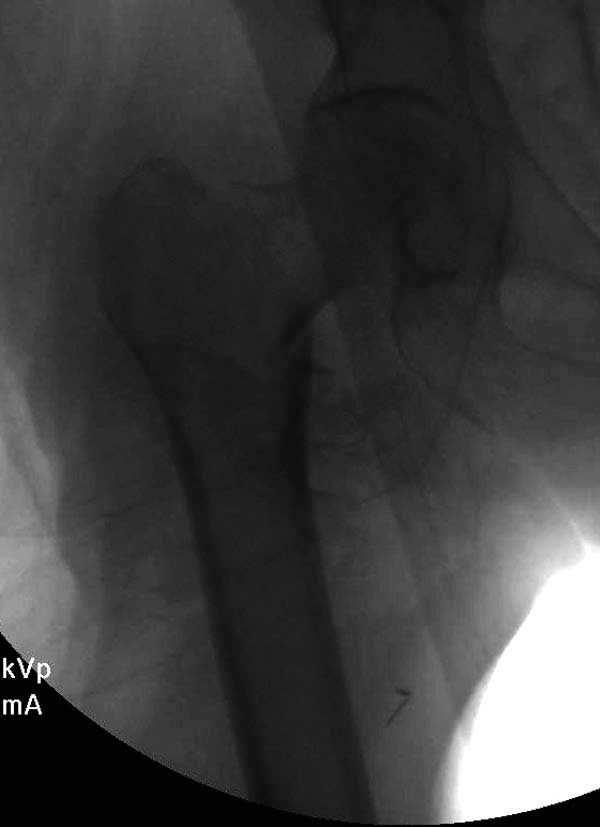

Третья операция-продолжения усилии "синьорами пэрами" по разрушению нормальной анатомии. Крест на головку! По видимому возраст позволяет биполярную конструкции, и при дефекте  calcar пошли на обычный цементный. Ягодичные мышцы потеряли связь с вертелом, т.е. отсутствует верхний удержатель, и результат “a Big Screw Up!” Снимки вызывают головокружение!

Если хирурги не устали от своих “творчеств”, тогда можно ре-оперировать с calcar replacement stem, и собрать остаток ягодичных мышц. Глубина и отстутствие артроза позволяет применить любой, биполярный или тотальный, хотя принять решение можно после ревизии ацетабулума.